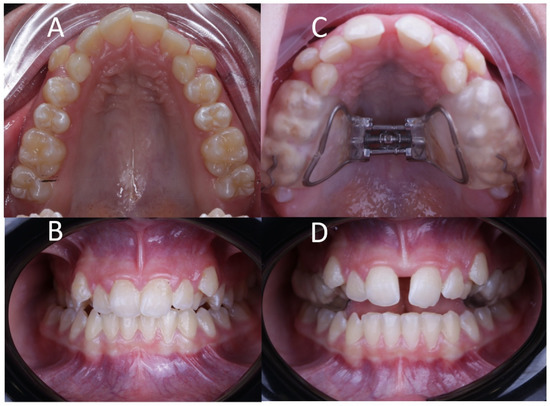

Figure 2.

(A) Right lateral, (B) left lateral, (C) bottom and (D) frontal view of the postoperative cone-beam computed tomography (CBCT) scans, aligned to the Frankfort plane and the midsagittal plane was perpendicular to the ground.